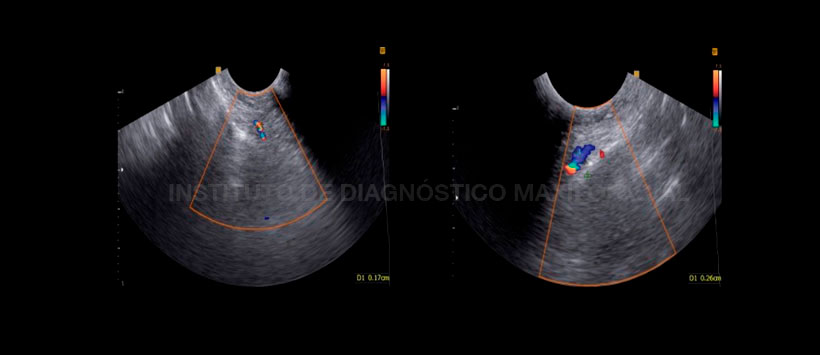

Por otro lado, el uso del ultrasonido Doppler color en el caso de infección sinusal ha sido sugerido para el diagnóstico de sinusitis maxilar. En base a estudios previos, se puede concluir que la corriente de sonido puede producirse en las secreciones sinupresoras del seno, pero no en las secreciones mucosas purulentas debido a su alta viscosidad. A diferencia de la sinusitis no purulenta en la sinusitis purulenta, el ultrasonido Doppler a color también muestra un aumento en el flujo sanguíneo. En consecuencia, las secreciones purulentas son distinguibles de las secreciones serosas sinusales.

La sinusitis es un proceso inflamatorio y la inflamación se ha asociado con un aumento del flujo sanguíneo. Por lo tanto, se puede formular la hipótesis de que en el momento de la sinusitis, las arterias que transportan sangre a los senos paranasales aumentan la velocidad y el diámetro del flujo sanguíneo para aumentar el flujo sanguíneo a los senos paranasales.

Figura 4: Diámetro normal (lado izquierdo) y anormal (lado derecho) de la arteria maxilar. Diámetro de más de 2 mm significa un aumento en el flujo de sangre al seno debido a la sinusitis (signo de Ghasemi).